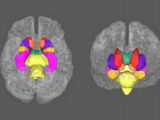

TMSの模式図。画像は「NIH」より引用今月5日、欧州神経精神薬理学会(European College of Neuropsychopharmacology)で発表された内容によると、研究者たちは統合失調症患者の幻聴に関わる脳の領域を発見し、経頭蓋磁気刺激法(TMS)による治療が3割の患者に有効であることが判明したという。TMSとは電磁石によって脳へ電気刺激を与える治療法で、頭痛やパーキンソン病などの神経症状や、うつ病などの精神症状を改善させることが知られている。

幻聴に関連しているとみられるのは、側頭葉の言語に関連する領域だった。26人の患者が2日にわたり、この部位に対してTMSの治療を受けた。そして2週間後に再検査したところ、患者の34.6%に症状の改善が見られたという。だが、長期的な効果についてはさらなる研究が必要だという。